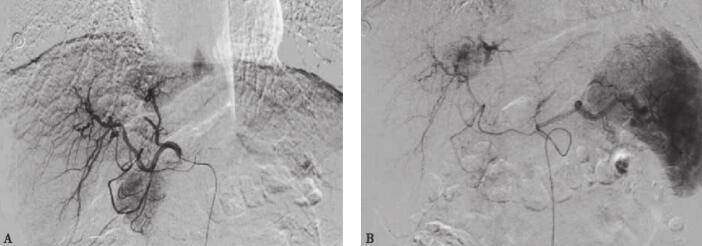

常规穿刺部位消毒铺巾,局部用2%的利多卡因5ml麻醉。按Seldinger技术规范,行右侧股动脉穿刺,“冒烟”显示导管位于动脉内,将导管头端置于腹腔干动脉造影,显示肝动脉增粗、紊乱,肝实质内近肝门区可见不规则异常肿瘤染色。导管头置于肝右动脉经导管给予盐酸表柔吡星20mg,奥沙利铂100mg行灌注术。再经导管给予奥沙利铂50mg与碘油8ml的混悬液行肝动脉化疗栓塞术。术后造影复查示:肝实质内可见碘油颗粒沉积良好,未见明显肿瘤染色(图2)。

图2 TACE术中图像